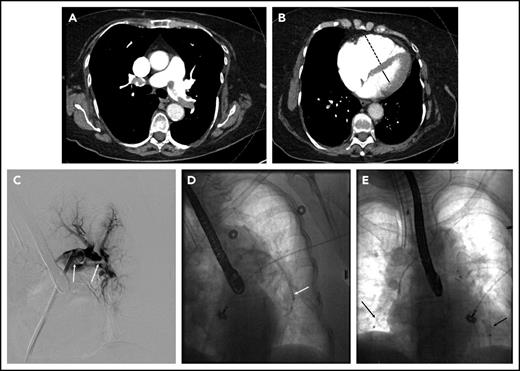

The patient was started on a therapeutic dose of UFH, and diagnostic testing for PE was initiated. Laboratory data included troponin-I of 0.35 ng/mL (normal < 0.04 ng/mL), an N-terminal-pro-brain natriuretic peptide level of 3590 pg/mL (normal < 300 pg/mL), and lactate 2.4 mmol/L (normal < 1.6 mmol/L). Chest computed tomography (CT) angiogram showed a saddle PE in the main pulmonary artery as well as obstructive lobar and segmental thrombus (Figure 1A-B). The RV to left ventricular (LV) ratio was 1.3 (normal < 0.9). Transthoracic echocardiography showed a severely dilated and hypokinetic right ventricle and an estimated pulmonary artery systolic pressure of 61 mmHg.

Submassive pulmonary embolism in patient 2. (A) Coronal CT demonstrating thrombus (arrows) in the right main and left lower-lobe pulmonary arteries. (B) Bulky thrombus is identified in the right lower-lobe pulmonary artery (arrow). (C) Wires and catheters traversing the thrombus in the right main and lower-lobe pulmonary artery. (D) Completion pulmonary angiography demonstrating good pulmonary perfusion.

The hospital’s Pulmonary Embolism Response Team (PERT), consisting of faculty from cardiothoracic surgery, pulmonary/critical care medicine, and interventional radiology (IR), was activated. After a discussion of treatment options, the PERT’s consensus was to proceed with CDT. In the IR suite, the pulmonary arterial system was catheterized (Figure 1C). The mean plasminogen activator (PA) pressure was 37 mmHg. Bilateral multisidehole infusion catheters were positioned within the thrombus. Recombinant tissue PA (rt-PA) was administered through each catheter at a rate of 0.67 mg/h (total dose 1.3 mg/h). UFH was infused through one of the sheaths to maintain a PTT less than 2 times the institutional norm during the infusion. After 18 hours (24 mg rt-PA total), the patient was brought back to the IR suite, where repeat measurements showed a mean PA pressure of 20 mmHg. Repeat angiography showed that the main right and left pulmonary arteries and lobar branches were largely thrombus free (Figure 1D). The sheaths and catheters were removed, and therapeutic-level UFH was resumed. An echocardiogram the next day showed improved RV function. He was discharged on warfarin 4 days postoperative. One month after discharge he reported feeling well without residual dyspnea or other symptoms.